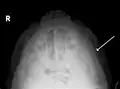

Fracture of the zygomatic arch as seen on plain X-ray- Zygomatic arch, base of skull